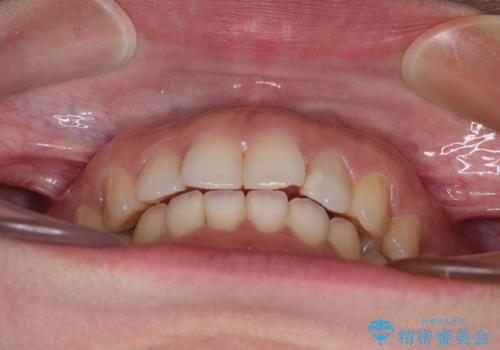

インビザライン矯正で前歯のデコボコを改善

- 前歯のデコボコを気にして来院された患者様です。

目立たないことを最優先にしたいとのことで、デコボコは軽度であったことから、インビザラインにて矯正治療を行うこととしました。

骨格的に下顎骨が左にずれており、上下の正中一致は困難ではありましたが、IPR(歯と歯の間を削る)や後方への移動など組み合わせて、できる限り改善しました。

インビザラインはマウスピースを外している時間が長いと、長期間使用しても前歯のデコボコはあまり改善されません。こちらの患者様は治療期間が長くなり、装着時間が短くなってしまったことで、気になる部分の改善により長期間を要するようになってしまいました。